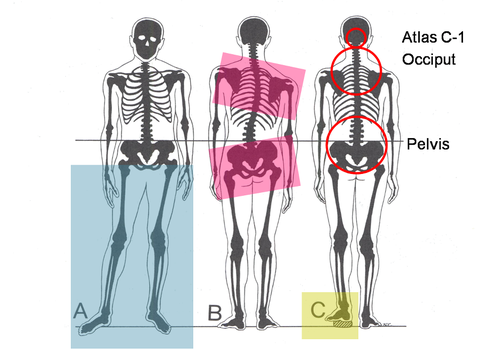

Duruş bozukluklarının fiziksel ve ruhsal olarak birçok soruna yol açabileceğini belirten Fiziksel Tıp ve Rehabilitasyon Uzmanı Dr. Esin Selimoğlu, yanlış duruş pozisyonlarının, boy kısalmasına dahi neden olabileceğini söyledi.